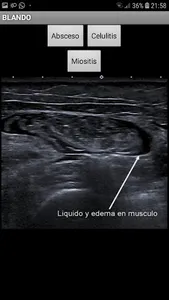

This application has several basic explorations of ultrasound at the foot of the bed. It has images, graphics and schemes to guide during the exploration. This application is about FAST, exploration of the gallbladder, TVP, Aorta, Cardiac, Vena Cava, Renal, Soft parts and links to webs on ultrasound at the foot of the bed and video channels in the youtube on ultrasound at the foot of the bed

ECOTUTOR Screenshots